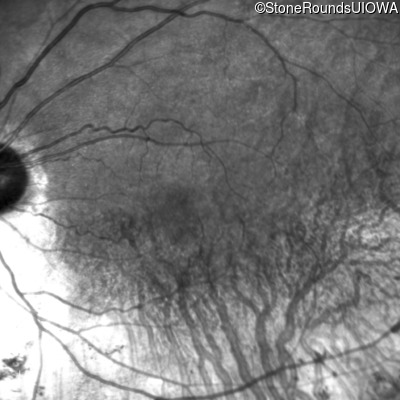

The clinical features supporting the diagnosis of autosomal dominant retinitis pigmentosa in this patient include: night blindness as her earliest symptom; an inferior sector of bone-spicule-like pigmentation and narrowed arterioles on fundus examination; a striking symmetrical superior visual field loss; loss of outer retinal structures on OCT; and, 2 similarly affected aunts, a brother and grandmother.

Age at visit: 57 years